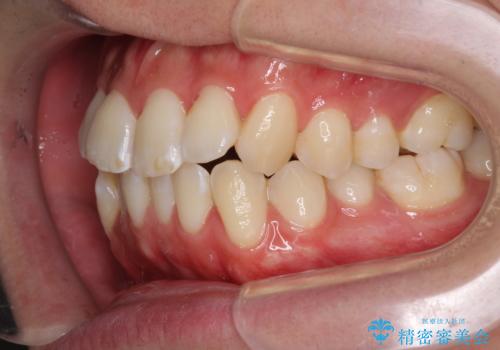

- 前歯のデコボコと若干口元が突出していることを気にして来院された患者様です。

全体的に軽微な叢生が認められ、口元もやや前方に突出していたため、インビザラインでのIPR(歯と歯の間を削る)と歯列全体の後方移動によって歯並びを整えることとしました。

上下ともに歯列の幅が狭かったため、側方に拡大することで前歯のデコボコや突出感を解消するためのスペースを獲得することができました。

歯並びが改善したことはもちろん、咬み合わせの改善まで実感することができ、患者様には大変満足していただけました。